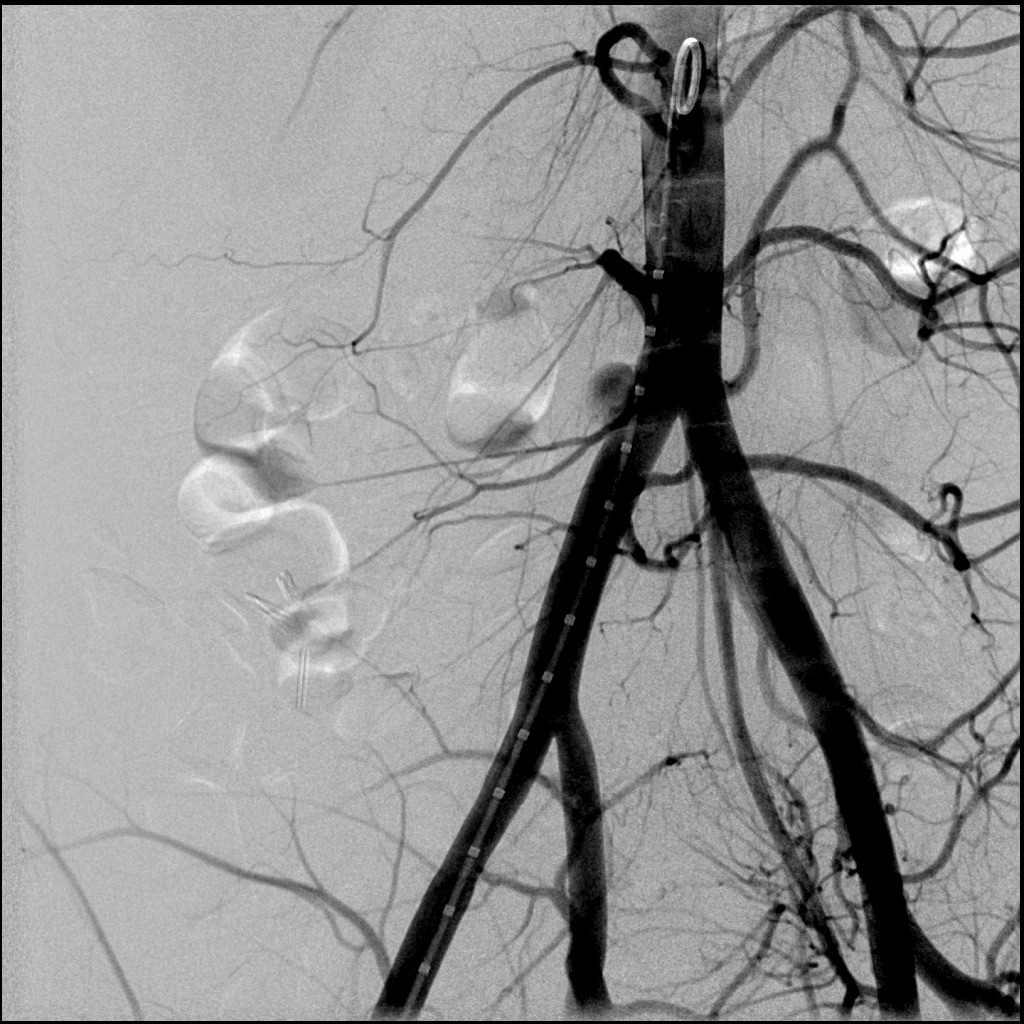

La radiologia interventistica è una moderna branca della medicina che si occupa del trattamento di un’ampia gamma di patologie attraverso un approccio minimamente invasivo, endovascolare o percutaneo, guidato da tecniche di imaging avanzato.